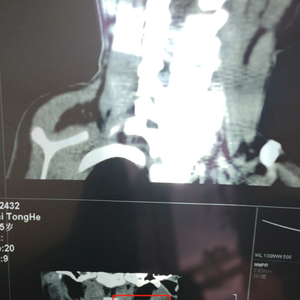

春末夏初,4月上旬,白先生依旧在带着孩子到处求医。“2023年,我们在北京儿童医院找到了针头的位置,在脖子,也就是颈部区那里。医院建议我们可以手术,但北京儿童医院床位紧张,需要等1到3个月,在此期间还要固定观察。”

2018年12月24日,白先生5个多月的孩子在星元医院做了鼻泪管探通手术,当天回家发现感染了,于是第二天开始输液治疗,并在星元医院办理了住院手续。“12月28日,护士来给孩子更换留置针,将留置针拔出后我家属发现针头导管断裂不见了,在病房中用了很多办法都没有找到。”白先生回忆,他们之后在医院做了B超,B超显示:左侧颞部头皮下有长约15mm的管状回声物,这意味着,针头导管可能断裂在了头部血管里。

经多方确认,发现留置针导管确实留在了体内,而星元医院没有能力解决这个问题,所以当天就派救护车和一名护士将孩子转送至西安市儿童医院,并再次做了B超检查,同样发现头部皮下有管状回声物。然而,孩子在接受手术取异物时,医生发现留置针导管不见了,可能因为血液流动改变了存留位置。手术后,医院再次做B超寻找留置针导管,却没能找到。

直到2023年,事情终于发生了转机:针头找到了。白先生称,虽然可以给孩子安排手术治疗,但风险很大。“因为做颈部手术的话,容易影响面部神经,造成娃娃面瘫等后果。同时血管血液流动,手术难度较大,并不能确认是否可以取出。”由于已经尝试过一次手术,失败后,孩子头皮留下8厘米左右长的疤痕,白先生表示已经无法承受手术再次失败的风险。“所以,我们还是选择继续观察,在此期间继续寻找权威机构进行手术。”